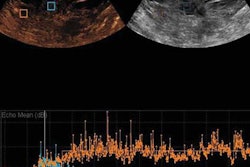

Left: Images of metastatic cervical lymph node. (A) Irregular low-echo nodules can be seen on conventional ultrasound, but the structure of the lymph node hilum is unclear. (B) Using "quality mode" on the VTIQ software, the lesion appears green with some yellow, showing good elasticity. (C) Using "velocity mode" on the VTIQ software, the shear-wave velocity values are shown for different points in the lesion. Right: Images of nonmetastatic lymph node. (A) An oval hypoechoic nodule can be seen on the conventional ultrasound, but the structure of the lymph node hilum is also unclear. (B) and (C), same descriptions as for previous image. All images courtesy of the Journal of Ultrasound in Medicine.False negatives